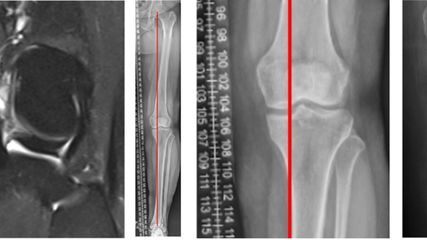

Seit 2021 werden in der Klinik für Unfallchirurgie und Orthopädie des Johannes Wesling Klinikums, Minden, ältere Patienten, die sich eine dislozierte mediale Schenkelhalsfraktur Garden III oder IV zugezogen haben, mit einer zementierten Kurzschaftprothese versorgt. Als Kopf wird entweder eine unipolare Pfanne oder eine zementfreie Pfanne implantiert. 2023 und 2024 wurde bei insgesamt 174 Patienten eine zementierte Kurzschaftprothese über einen Watson-Jones-Zugang in Rückenlage implantiert. Das Durchschnittsalter lag über 80 Jahre. Es wurden mehr Frauen als Männer behandelt (67,2% weiblich, 32,8% männlich). Fast 70% der Patienten fielen in die ASA-Klassifikation Grad 3 (1,1% ASA 1; 21,3% ASA 2; 70,1% ASA 3; 6,9% ASA 4; 0,6% ASA 5). Insgesamt 84,5% der Patienten erhielten eine Hemiendoprothese, während 15,5% mit einer Totalendoprothese versorgt wurden (Abb. 3,4). Nach der postoperativen unfallchirurgischen Behandlung wurden die Patienten entweder in eine geriatrische Klinik innerhalb oder ausserhalb des Krankenhauses verlegt oder es erfolgte eine stationäre Anschlussrehabilitation. Bis zum Zeitpunkt der Entlassung musste bei vier Patienten aufgrund einer prolongierten Wundsekretion eine Wundrevision durchgeführt werden. Im Rahmen der postoperativen Mobilisation kam es bei einem Patienten zu einer Luxation, die nach Reposition konservativ behandelt wurde. Die operierten Patienten werden aktuell zur Nachuntersuchung eingeladen.

Abb. 3: 81-jährige Patientin mit nach Sturz dislozierter Schenkelhalsfraktur Garden IV rechts